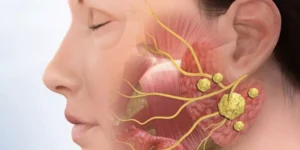

الأورام النكفية هي نمو غير طبيعي للخلايا يبدأ في الغدد النكفية. وتتكون العدد النكفية من غدتين لعابيّتين تقعان أمام الأذنين مباشرة واحدة على كل جانب

أورام الغدد اللعابية هي نمو غير طبيعي للخلايا يبدأ في الغدد اللعابية. وتتميز أورام الغدد اللعابية بندرتها. تفرز الغدد اللعابية اللعاب. ويساعد اللعاب على الهضم